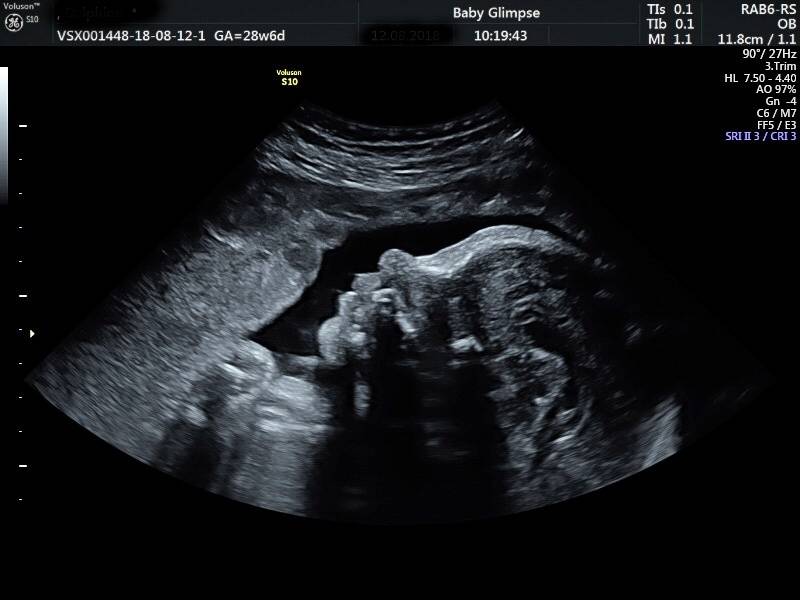

Wij maken jouw kennismaking magisch

Zwanger zijn is iets magisch. En dat prachtige gevoel willen wij nastreven in onze praktijk. Onze echoscopisten hebben een verloskundig achtergrond en werken daarnaast met de beste apparatuur. Ook hebben wij de leukste samenwerkingen met de mooiste merken waar jullie van kunnen profiteren. Dit alles zorgt voor een geweldige ervaring. Tot snel bij Baby Glimpse…